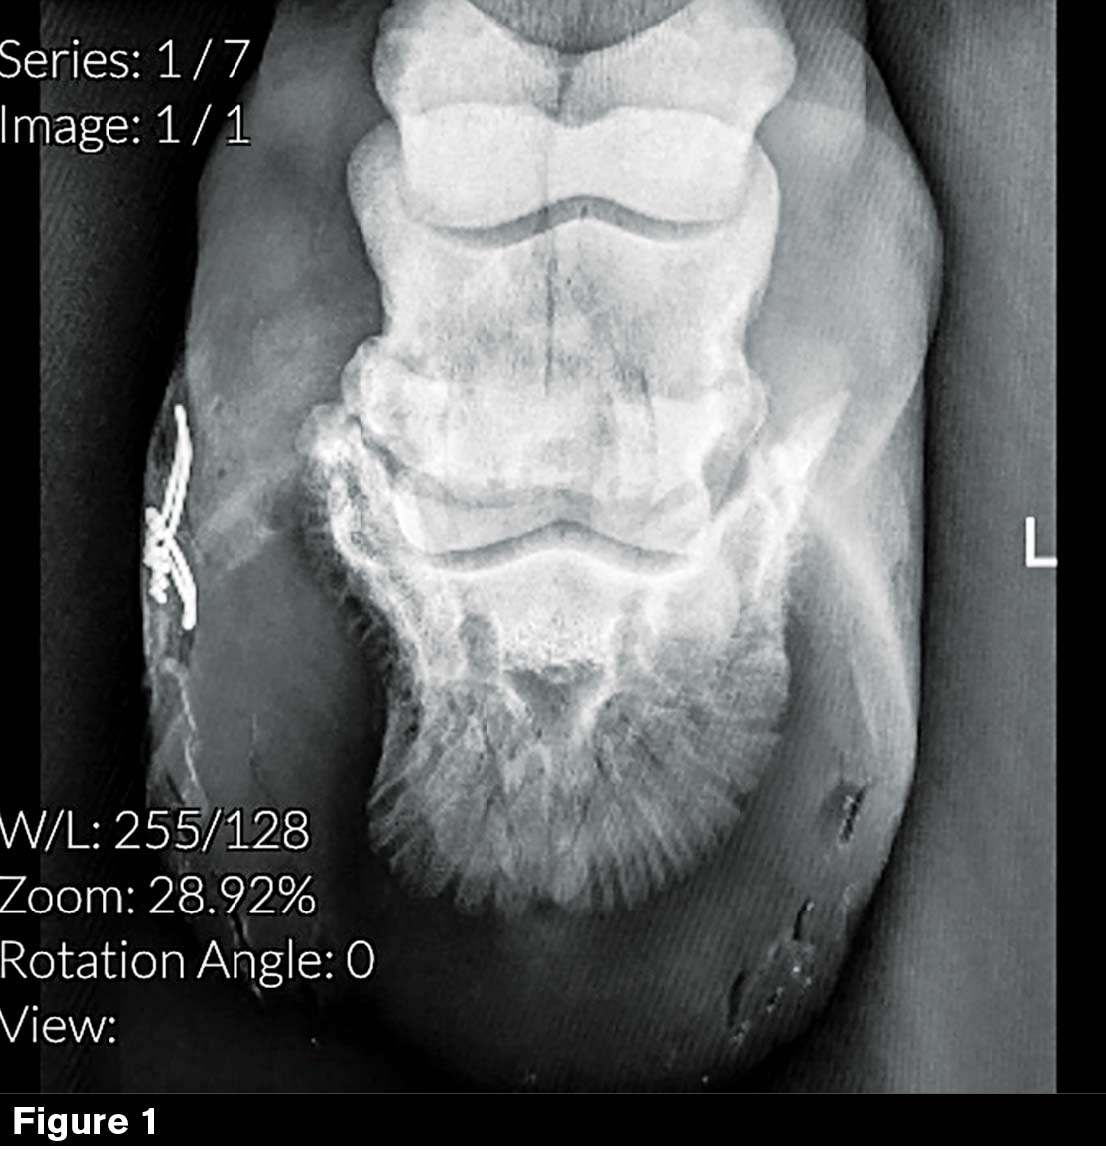

“He’s missing probably 20% to 25% of his coffin bone on the medial side of the left front foot (Figure 1),” says Jan Henriksen, an equine veterinarian at B.W. Furlong & Associates in Oldwick, N.J.